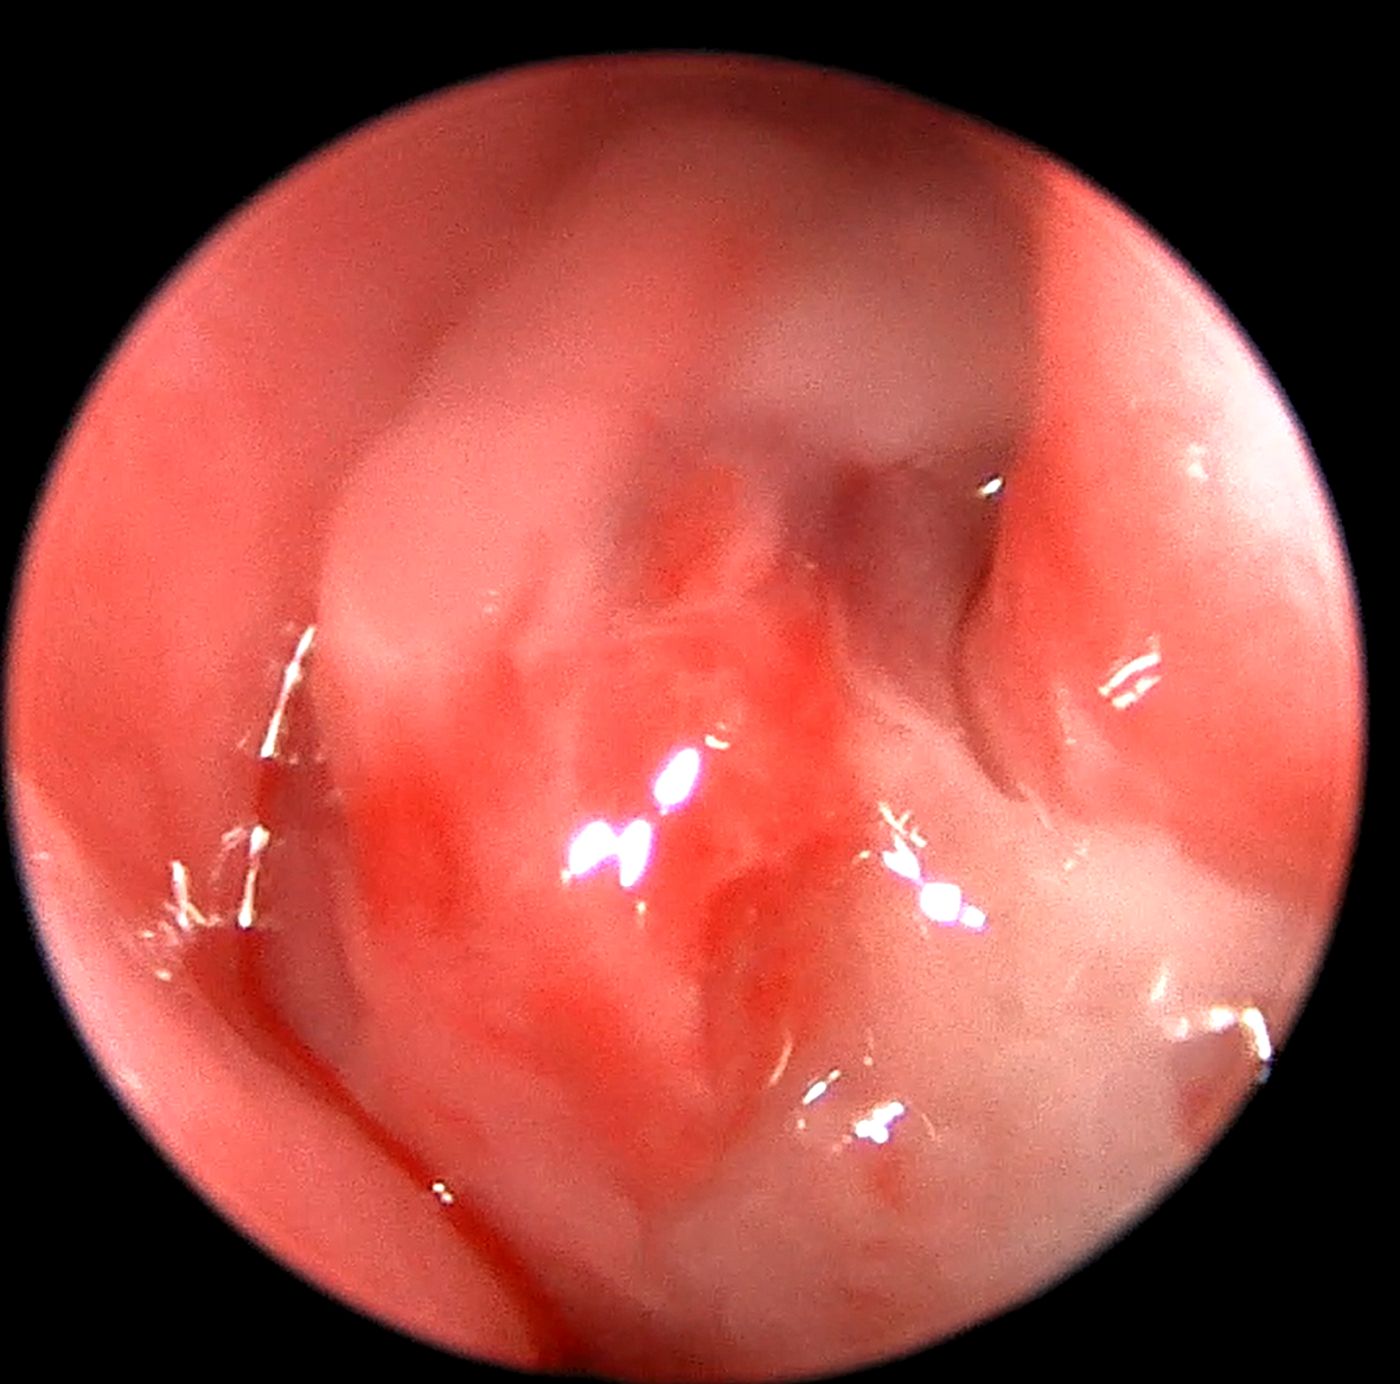

Diagnostyka endoskopowa jamy nosowej (rinoskopia przednia, rinoskopia tylna)

Zalecana w przypadku:

Przewlekły (ropny, śluzowy) wypływ z nosa

Krwotok lub kropelkowanie krwi z nosa

Trudności z oddychaniem

Asymetria jam nosowych, obrzęk okolicy nosa

Podejrzenie zmian rozrostowych

Ciała obce

Wykonujemy:

Diagnostykę z pobraniem próbek do badań mikrobiologicznych oraz histopatologicznych

Resekcję zmian nowotworowych w obrębie jam nosowych

Leczenie stenozy nosogardzieli

Usuwanie polipów zapalnych

Leczenie grzybicy jam nosowych